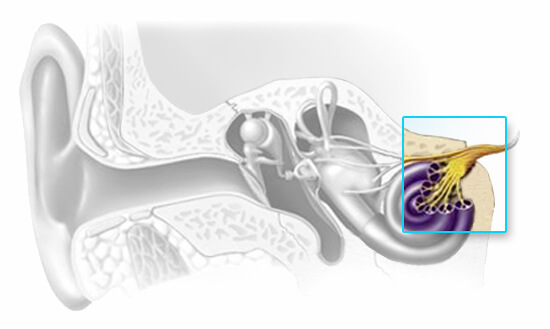

Sensorineural hearing loss results from inner ear or auditory nerve dysfunction. The sensory component may be from damage to the organ of Corti, an inability of the hair cells to stimulate the nerves of hearing or a metabolic problem in the fluids of the inner ear. The neural or retrocochlear component can be the result of severe damage to the organ of Corti that causes the nerves of hearing to degenerate or it can be an inability of the hearing nerves themselves to convey neuro chemical information through the central auditory pathways.

The reason for sensorineural hearing loss sometimes cannot be determined, it does not typically respond favorably to medical treatment, and it is typically described as an irreversible, permanent condition. Like conductive hearing loss, sensorineural hearing loss reduces the intensity of sound, but it might also introduce an element of distortion into what is heard resulting in sounds being unclear even when they are loud enough. Once any medically treatable conditions have been ruled out, individuals with a sensorineural hearing loss can be fit with hearing aids to give them access to speech and other important sounds.